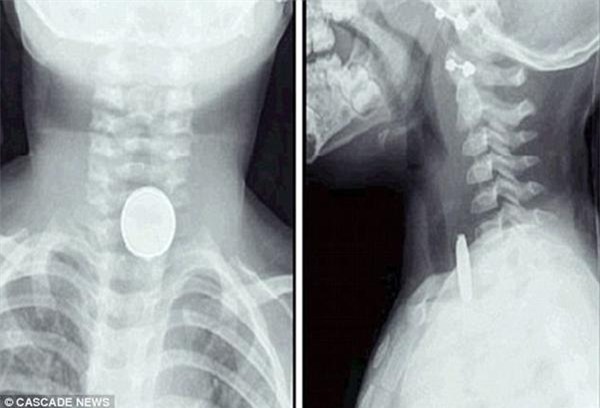

Theo đó, bé gái Molly - con chị Jane đã tự tay tháo cục pin nhỏ xíu trong chiếc điều khiển xe đồ chơi của anh trai và nuốt nó vào miệng. Cô bé được phát hiện kịp thời và lập tức chuyển tới bệnh viện.

Sau cuộc phẫu thuật căng thẳng, Molly đã sống sót. Các bác sĩ cho biết cục pin bị tắc ở thực quản của Molly và nó có thể khiến cô bé mất mạng nếu kéo dài trong vòng 1 giờ đồng hồ. Tuy cuộc phẫu thuật thành công nhưng cục pin ảnh hưởng không nhỏ đến dạ dày của Molly nên cô bé phải dùng thuốc trong vòng 6 tuần để sức khỏe hoàn toàn bình phục.